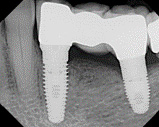

Зубной мост на имплантатах представляет собой несъемную конструкцию, видимая часть которой состоит из нескольких, объединенных между собой в единый блок, искусственных зубов, имеющих внутренние крепления – дентальные имплантаты.

При одновременной опоре моста с одной стороны на имплантат, а с другой - на живой зуб, следует учитывать, что разные опоры имеют разную степень фиксации в кости:

В процессе ношения протеза такие различия создают некоторый амортизационный эффект, который дестабилизирует равномерное распределение нагрузки и, в итоге, приводит к расшатыванию опор.

Поэтому ортопеды рассматривают такой вариант крепления моста крайне нецелесообразным.